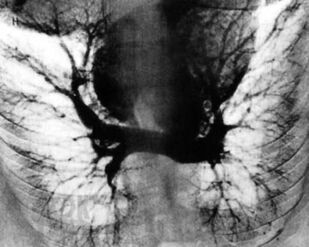

В монографии представлены важнейшие хронические заболевания легких у детей, рассмотрены вопросы терминологии и классификации этих болезней. Описаны клинические проявления различных форм хронической бронхолегочной патологии, даны критерии и современные методы диагностики. Отдельные главы посвящены хроническим воспалительным заболеваниям легких, врожденной и наследственной патологии, бронхиальной астме, интерстициальным болезням легких, грибковым поражениям бронхолегочной системы. Рассмотрены особенности течения туберкулеза при хронических неспецифических заболеваниях легких. Изложены принципы терапии хронических заболеваний легких у детей. Книга адресована педиатрам, пульмонологам, аллергологам, врачам общей практики, сотрудникам научно-исследовательских учреждений и учебных заведений.